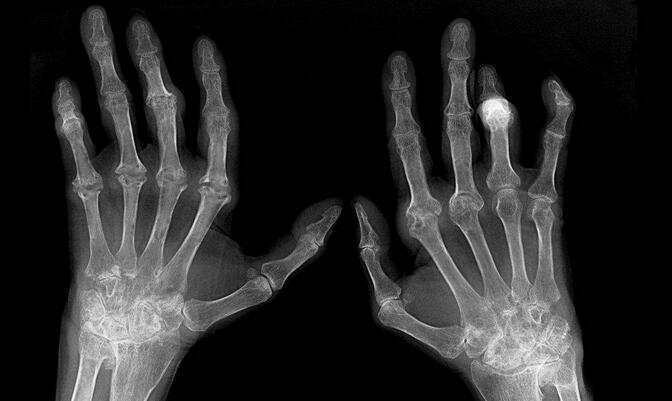

类风湿性关节炎的新认知,关于类风湿哪些传统观念是有问题的

(1)传统观点:所有根据美国风湿病学会(ARA)制定的RA分类标准所诊断的RA,都有相似的病理过程和预后。现代观点:根据ARA标准诊断的RA至少有三种不同的病理过程和预后,部分呈持续性,部分恶化。

(5)传统观点:RA是一种预后较好的疾病,病情可以自愈。现代观点:多数RA病人有严重的功能减退,骨质进行性破坏,工作能力的下降和在3~5年内死亡率的增加。